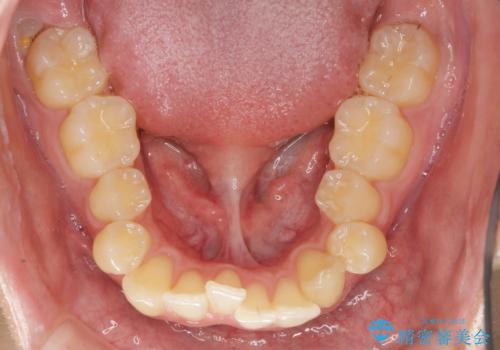

過蓋咬合・上顎前突・叢生を改善するマウスピース矯正

- 前歯のがたつき、不揃いさの改善を求めて来院されました。

・前歯の深い噛み合わせ (過蓋咬合)

・上顎前突(Angle Class2)

・叢生(がたつき)

20時間以上のマウスピース装着、ゴムかけを遵守していただいたおかげでしっかりと噛み合わせ、がたつきの改善を行うことができました。